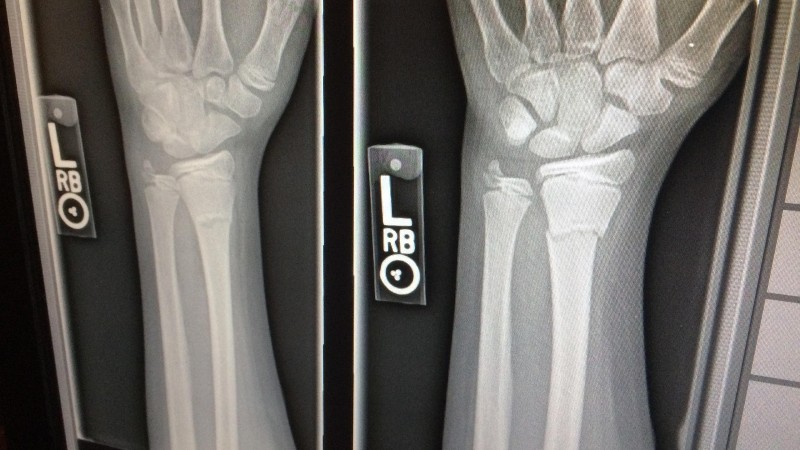

It doesn’t matter if it’s chronic or not; even a broken arm which is completely healed is a “pre-existing condition”.

ExpatDen: About a broken arm, in practice, do insurers usually exclude minor past issues like a fully healed broken bone or short-term infections?

Carsten: Yes they do, because in their “world” it is still a pre-existing condition.